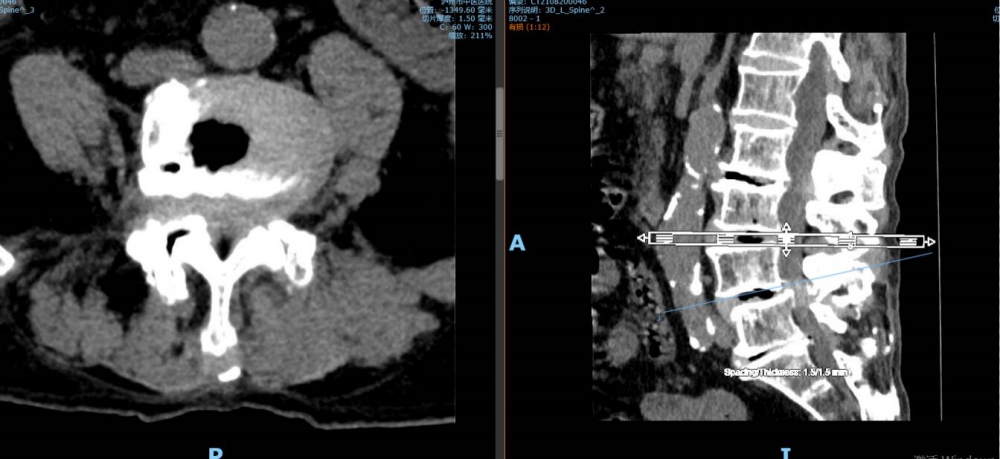

腰4 5椎间盘CT

腰4 5椎间盘MRI

泸州市中医医院骨伤二科主治中医师胡建超介绍,李谨行老人患有腰椎管狭窄症 、腰4椎I°滑脱 、脊柱退行性侧弯畸形 、冠状动脉粥样硬化性心脏病、心律失常、高血压2级等17种疾病,同时处于慢性阻塞性肺病加重期和脑梗塞恢复期。92岁、全身多种疾病,随时可能会有突发情况,要做这样一个大手术,对医生和患者来说,无疑都是一个巨大的挑战。